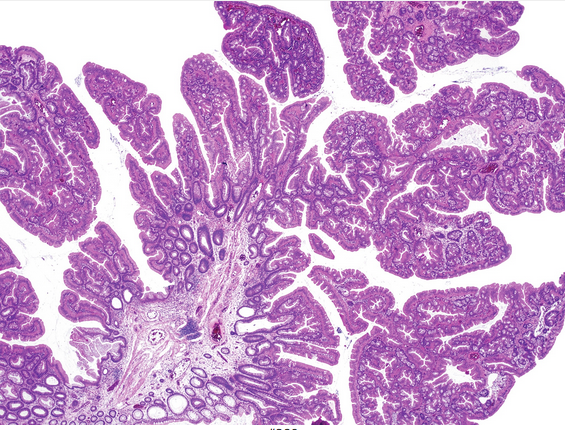

Rectal specimen. Hx of PR bleeding.

Dx? + description?

solitary rectal ulcer syndrome/mucosal prolapse.

Fibromuscular hyperplasia/obliteration of lamina propria

Architectural distortion of colonic mucosa/epithelium

Hyperplastic/villiform, regenerative surface with mucin loss

Inflammation, erosion, ulceration, pseudomembranes

Capillary proliferation with dilation below surface

Dense submucosal fibrosis with cysts often present

High-power magnification of an H&E-stained section shows characteristic hyperplastic, villiform surface epithelium ; disorganized smooth muscle fibers in the lamina propria ; and proliferating, congested capillaries in the superficial lamina propria.